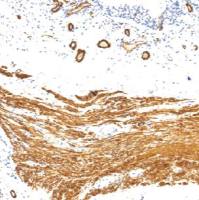

Product Image |

|